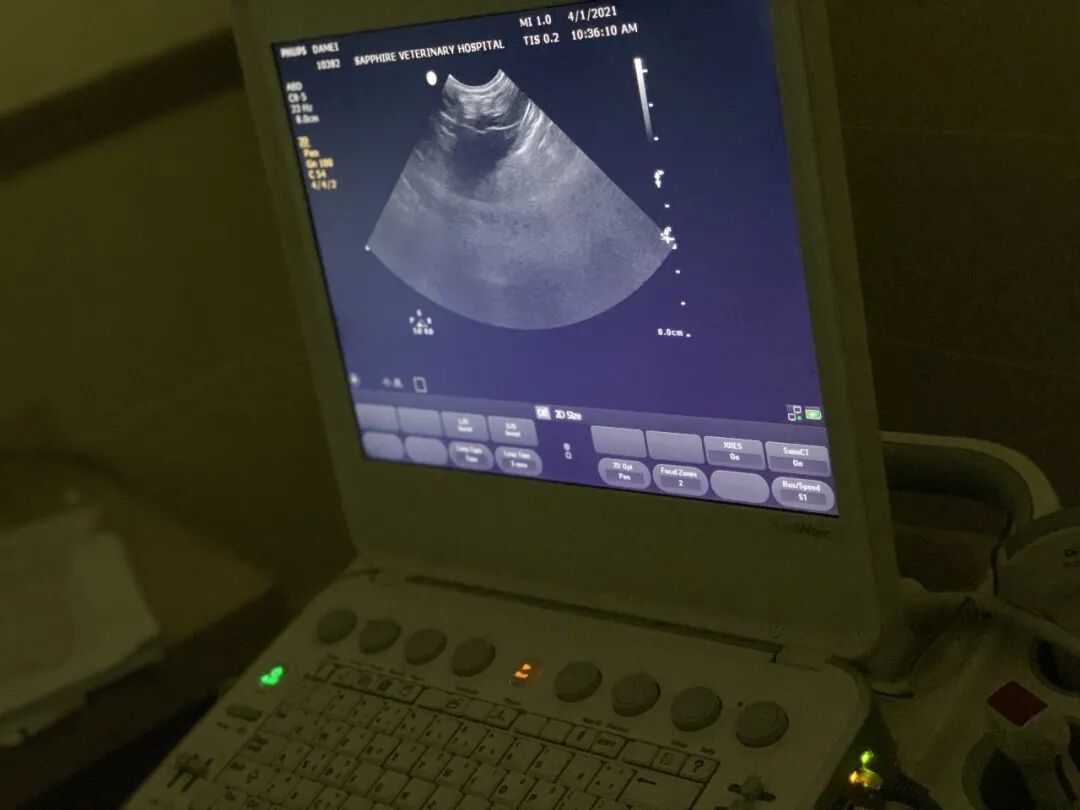

中暑的表现某种程度上和心脏病发作有一定的相关和相同处。判断猫咪是否中暑需要先排除猫咪是否患有心脏病,在猫咪没有心脏病的情况下,夏季气温升高出现以下表现,则可能是中暑。